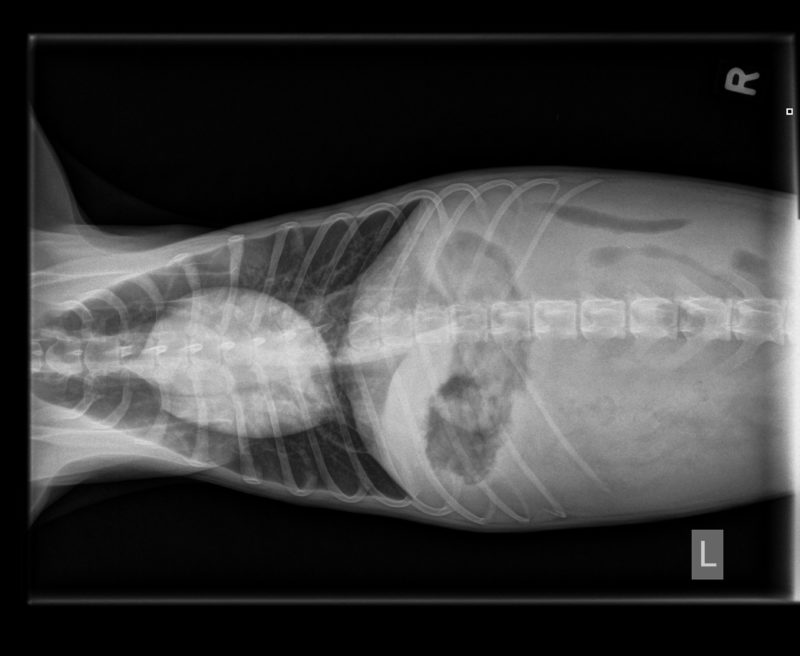

Als erste Diagnostik wurde der Hündin Blut abgenommen, um einen Blutstatus (u.a. rote und weiße Blutkörperchen, Hämatokrit, etc.) zu erstellen. In der Zwischenzeit wurde ein Röntgenbild des Abdomens erstellt. Auf dem Röntgenbild war eine hochgradige Aszites (Flüssigkeitsansammlung in der Bauchhöhle) zu sehen, daher war das Abdomen nicht wirklich beurteilbar und aufgrund dessen wurde ein Ultraschall angesetzt. Hier zeigte sich, dass die Blase geringgradig Urinsediment aufwies, die Nieren sowie die Milz waren makroskopisch unauffällig, die Leber war deutlich verkleinert und inhomogen, die Gallenblasenwand erschien geringgradig verdickt. Die Dünndarmschlingen waren etwas hyperechogen und zeigten eine verdickte Mukosa, bei erhaltener Darmschichtung. Es erfolgte eine ultraschallgeführte Punktion der Bauchhöhle, um ein Probe der Bauchhöhlenflüssigkeit zu bekommen. Diese war makroskopisch wie Wasser ohne Hinweise auf Blutbeimengungen oder einem besonderem Geruch.